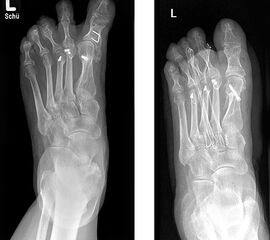

Angeborene Deformität und Fehlanlage 1. Strahl (eigenes Bildmaterial) (Vispo-Seara 1998, Hefti 1998)

Abbildung 9

Mit zunehmendem Wachstum und Alter wird die Abweichung der Großzehe zunehmend symptomatisch. Es können keine normalen Schuhe getragen werden, es entstehen kosmetisch schwerwiegende Probleme. Deshalb wird zu einer frühzeitigen Korrektur im Säuglings- und Kleinkindalter geraten 12, d. h. im 9. – 24 Lebensmonat 215.

Die Therapie ist immer operativ, wobei sich der individuelle Eingriff an der jeweiligen Dysplasie orientiert.

Gute Erfolge zeigen die Entfernung akzessorischer Knochen (Mc Elvenny, 1941; Corte-Real, 1998), sowie eine iatrogene Syndaktylie zwischen der 1. und 2. Zehe.

Möglich sind weiterhin subkapitale Osteotomien des Metatarsale I sowie eine auf- klappende Osteotomie am Os cuneiforme mediale (Hefti, 1998) mit K-Draht-Fixation oder die 1958 von Farmer 5 beschriebene Technik mit ausgeführter Lappentechnik (de Valentine, 1992).

Sinn jeglicher Prozedur ist das Schaffen eines reorientierten belastungsfähigen Fußes, welcher schmerzfreies Gehen ermöglicht. Eine Rezidivneigung besteht bei allen Gelenk erhaltenden Operationen am Vorfuß.